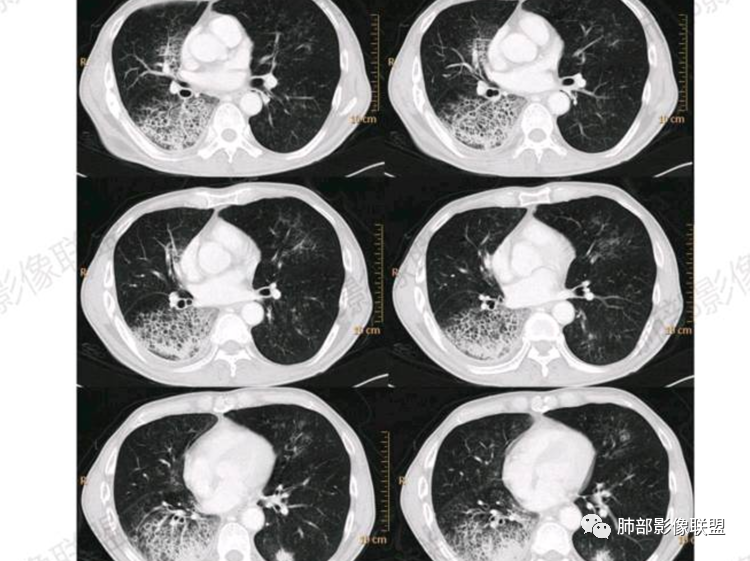

右肺弥漫实变浸润影➕小网格影,累及各叶段,实变部分位于胸膜下,明显均匀强化,内部血管影稀疏。

右肺体积缩小,右侧胸廓略塌陷,右肺中上叶多发簇状囊性影,大小不一,伴有间质增厚,胸膜下及脊柱旁多发实变影,宽基底与胸膜相连,平扫密度均匀,增强中等强化,左肺伴有散在斑片状磨玻璃影。

胸部CT:肺气肿,右肺上叶大片团片影,中叶纵隔侧小片影,下叶大片团片影;实变+磨玻璃+蜂窝,边界较清,小叶内间隔增厚,边缘膨隆为主,长轴平行于胸膜;实变区明显均匀强化,内部血管影稀疏。左肺上、下叶结节灶。老年病人,慢性病程,大量白色泡沫痰,肺部病灶重力分布、胸膜阻隔、左肺转移

CT:右肺弥漫实变影及磨玻璃影,内见小网格影及蜂窝影,病灶由胸膜下向外进展,明显均匀强化。

无明显肺气肿背景下右侧GGO+实变中见蜂窝征

实变区在胸膜下,部分边缘膨隆,凸向胸壁

2.影像显示右肺较广泛蜂窝样阴影,上肺及下肺为主,未见液平及重力分布趋势。其中上叶后段及下叶后基底段近胸膜下可见实性密度区,实性密度区强化明显,周边特征掩盖不清。

3.病灶区叶段支气管显示较满意,未见明显狭窄、阻塞或截断。

4.左肺偶见小结节,但未见典型播散结节影。注意左肺未见蜂窝影。

5.纵隔轻度右移,提示右肺体积整体轻度减小。

6.纵隔未见增大淋巴结。右肺门掩盖。